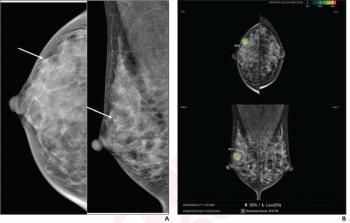

[[{"type":"media","view_mode":"media_crop","fid":"11554","attributes":{"alt":"Stephen Rose","class":"media-image media-image-left","id":"media_crop_8501769795264","media_crop_h":"0","media_crop_image_style":"-1","media_crop_instance":"218","media_crop_rotate":"0","media_crop_scale_h":"0","media_crop_scale_w":"0","media_crop_w":"0","media_crop_x":"0","media_crop_y":"0","style":"margin: 5px; float: left;","title":" ","typeof":"foaf:Image"}}]]In February 2011, the FDA approved the first X-ray mammography system that provides 3-D images for breast cancer screening and diagnosis,

In this podcast, Stephen Rose, MD, president and CEO of Houston Breast Imaging and a principal investigator of the 3-D tomosynthesis clinical trials in 2010, discusses the benefits of the new technology and what his practice learned when implementing the screening program. .